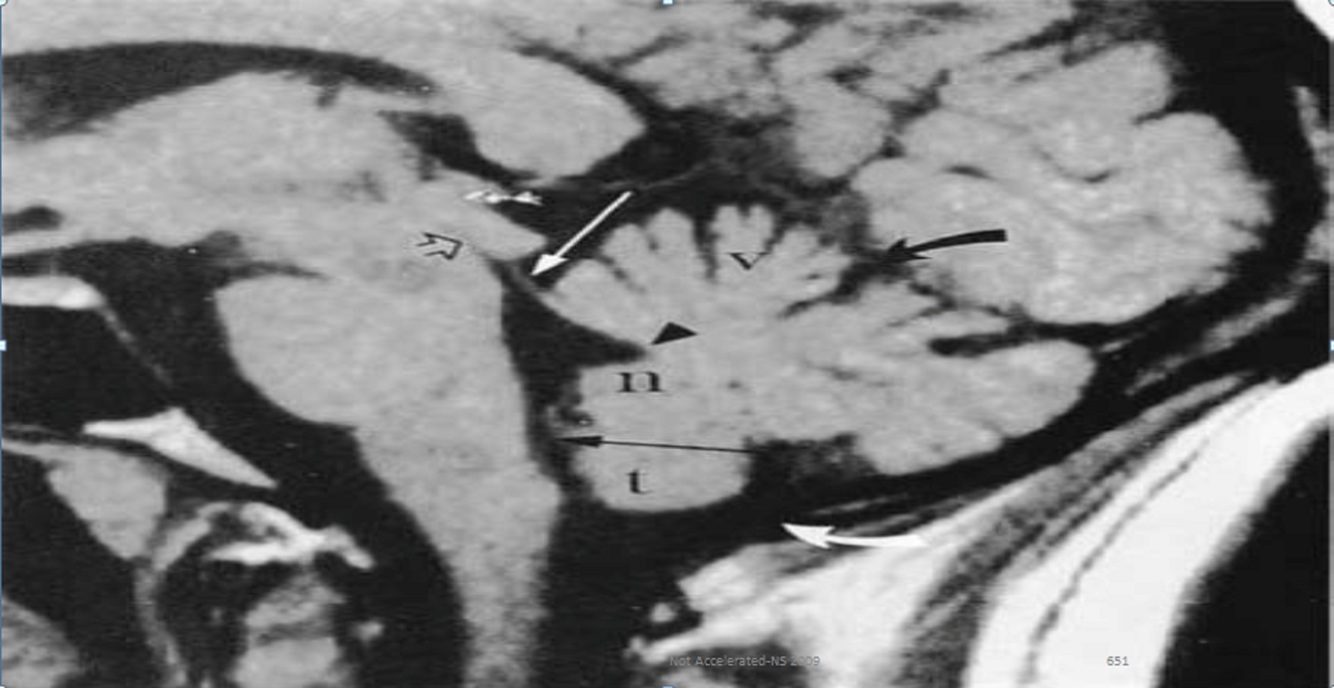

Seorang anak laki-laki 12 tahun menunjukkan riwayat sakit kepala general selama 6 bulan dan 3 bulan riwayat episode unrespon. Episode ini seringkali didahului oleh rasa kecemasandan berlangsung beberapa menit setiap kejadian. Pemeriksaan neurologis normal. MRI ditunjukkan figure 8A telah didapatkan. Manakah pernyataan dibawah ini yang benar ?

A.Cyst pritoneal shunting bukan merupakan terapi yang tepat

B.Abnormalitas primer adalah kegagalan perkembangan lobus temporal

C.Diagnosa yang paling tepat adalah kista arachnoid

D.Craniotomy untuk menghilangkan massa secara lengkap dan fokus epilepsi merupakan indikasi

E.Diagnosa yang paling tepat adalah tumor epidermoid

C